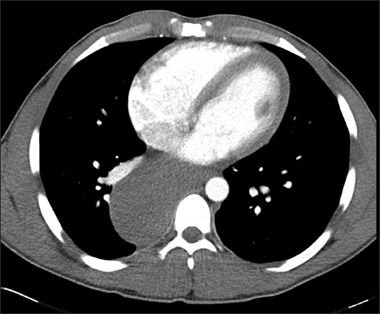

An abdominal radiographic series showed a right mediastinal soft tissue abnormality, prompting a CT scan of the chest. This showed a large 9 × 5.4 × 10-cm smoothly marginated, hypodense, homogeneous mass that emanated from the azygoesophageal recess and extended along the right aspect of the posterior mediastinum and aorta, displacing the right lower lobe of the lung and esophageal lumen. The mass was consistent with the diagnosis of a bronchogenic cyst-with esophageal duplication cyst, neuroenteric cyst, lymphangioma, and pericardial cyst included in the differential.